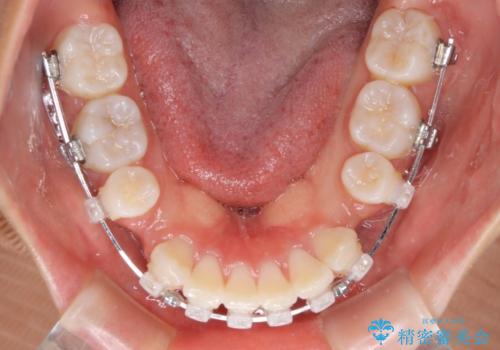

- クリアブラケット

- 1年7ヶ月

- 10-30回